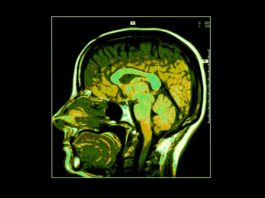

La revisione critica e sistematica della letteratura scientifica inerente gli effetti scheletrici dell’acromegalia, ha dimostrato che la fragilità scheletrica è una complicanza dovuta all'elevato turnover osseo e comporta un elevato rischio di fratture vertebrali, anche in presenza di valori normali o addirittura aumentati di densità minerale ossea misurata con tecnica MOC DEXA

Acromegalia

L'acromegalia è causata dall’ipersecrezione cronica di ormone della crescita GH che determina l'aumento della dimensione delle ossa delle estremità del corpo e di alcuni organi